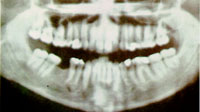

แพนอรามิกเดนทัลเรดิโอกราฟี (Panoramic Dental Radiography)

เราอาจถ่ายเอกซเรย์ฟันทั้งปากได้อีกวิธีหนึ่ง โดยสร้างหลอดเอกซเรย์ให้เล็กมากขนาดนิ้วมือ ให้รังสีเอกซ์ออกมาจากตรงปลายหลอด เอาหลอดเอกซเรย์ยื่นเข้าไปในปาก และเอากล่องใส่ฟิล์มอย่างอ่อนและโค้ง มาหุ้มรอบปาก รังสีเอกซ์จากหลอดเอกซเรย์ในปาก จะวิ่งทะลุฟันและผนังปาก ย้อนกลับออกมากระทบฟิล์ม เอกซเรย์ในกล่องภาพที่ได้ จะเป็นภาพขยายที่โตกว่าขนาดจริงของฟัน แสดงภาพของฟันทุกระนาบรวมกัน จึงเหมาะที่จะใช้ถ่าย เพื่อหาฟันผุมากกว่าแพนอรัลโทโมกราฟี

ฟิล์มเอกซเรย์ฟัน แสดงภาพฟันทุกระนาบรวมกัน โดยใช้เครื่องแพนอรามิกเดนตัลเรดิโอกราฟี

ฟิล์มเอกซเรย์ฟัน แสดงภาพฟันทุกระนาบรวมกัน

หนังสือสารานุกรมไทยสำหรับเยาวชน ฯ เล่ม 9